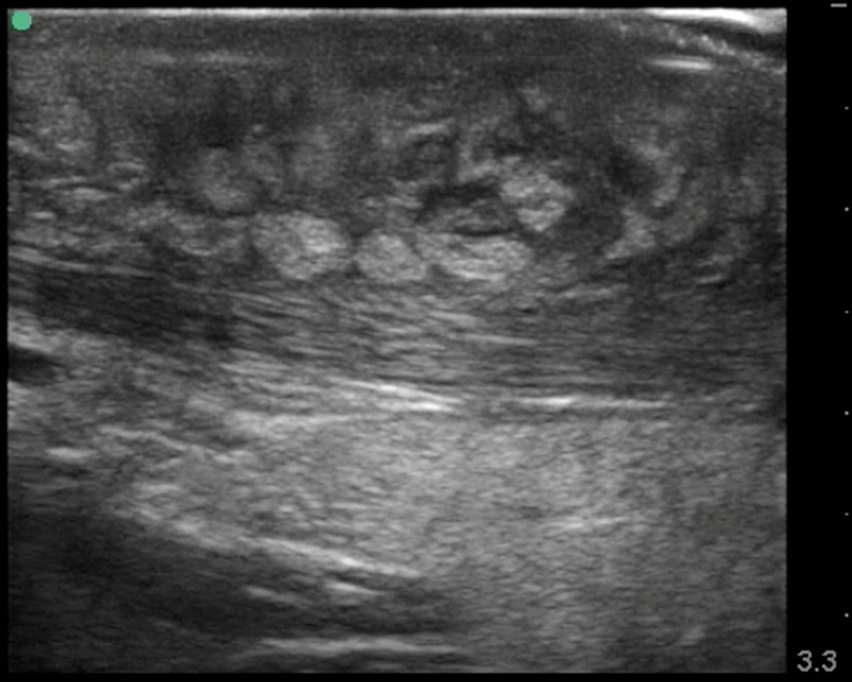

What is this image showing?

a abscess

What are the characteristics of an abscess?

elevated WBC, fever, red, and hot to the touch